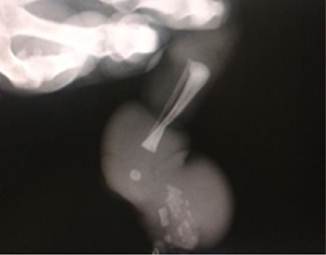

A las 33 semanas, en una junta médica se consideró que, aunque la extremidad distal al anillo presentaba vascularización, había dudas si estaba con isquemia crónica y en qué momento se volvería crítica para la vitalidad distal del miembro, por lo que después de un ciclo de maduración pulmonar fetal, se realizó cesárea obteniéndose un producto de sexo masculino, peso 1 800g, APGAR: 8 al minuto 9 a los cinco minutos. El examen físico posnatal confirmó el anillo constrictor en 1/3 inferior de miembro inferior izquierdo que causaba edema importante de la extremidad distal. No se observó signos de isquemia en ese momento (Figura 3).